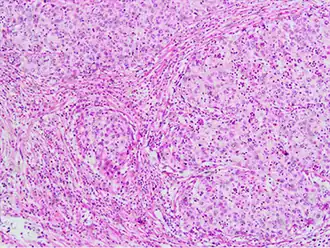

Invasive squamous cell carcinoma of the cervix is characterized by infiltration as irregular anastomosing nests or single cells.[75] This case is poorly differentiated. H&E stain. -

Invasive cervical squamous cell carcinoma on H&E histopathology and Ki-67 immunohistochemistry. The latter correlates well with the degree and level of dysplasia.[77] -